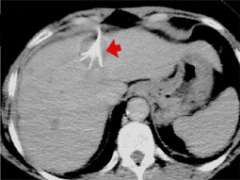

In radiofrequency ablation, a needle probe under ultrasound, CT, or even MRI guidance is inserted into the center of the liver tumor (fig.1). An alternating current (oscillating in the radiofrequency spectrum, hence the name) is applied through the needle, which passes through tissue to grounding pads placed on the thighs or to another electrode. As the current passes into the tissue at the needle tip, ionic agitation creates frictional heating in the tissue and tumor cells are killed.